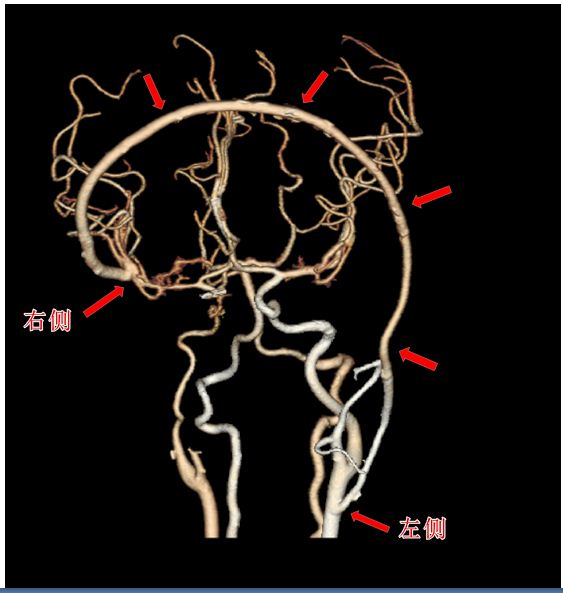

今年5月中旬,港大深医神经外科何伟成顾问医生、吴平安副顾问医生、袁国艳医生团队为叮当进行了“左侧颈总动脉-右侧大脑中动脉搭桥”手术。医生先从叮当的小腿取出一根长40多厘米的静脉,然后把这段血管的一头连接到左侧的颈总动脉,血管的另一头连接(搭桥)到右侧大脑中动脉。

用于搭桥的这根长长的血管横跨叮当的左右两个大脑半球,在小孩身上这种跨颅搭桥,文献尚无报道,在深圳属于首例。来自香港的神经外科何伟成顾问医生表示,2018年1月在港大深圳医院完成了深港首例成年人的类似跨颅搭桥手术,当时是为一名50多岁的鼻咽癌患者进行治疗,手术顺利完成。而这次由内地和香港医生联合完成的手术,是深港首例儿童跨颅搭桥病例。叮当的手术一共进行了7个小时,顺利完成。